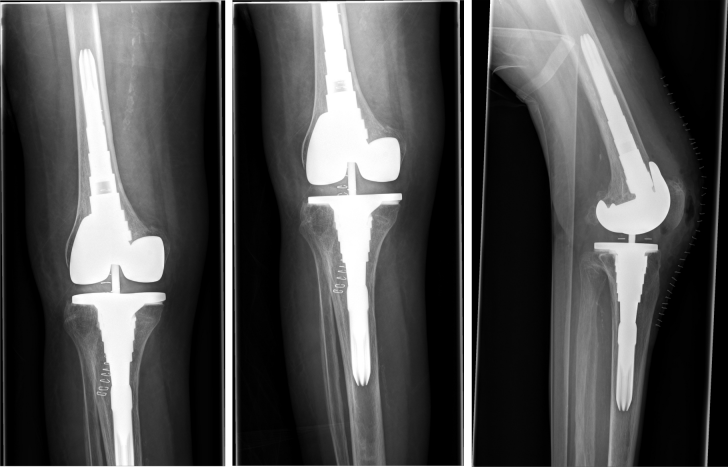

Figure 2: Postoperative x-ray of the right knee joint showing the correct position of the semi-constrained total knee replacement

This is a report on a female patient aged 84 years at time of surgery. The patient was admitted to our center due to right-sided gonarthrosis with partial instability of the collateral ligaments and compression fracture of the medial femoral condyle (Figure 1 [Fig. 1]). In addition, she had rheumatoide polyarthritis. Therefore, we performed total knee replacement (Figure 2 [Fig. 2]) using a valgus-varus constrained LCS-Complete™ Revision System (DePuy Synthes, 325 Paramount Drive, Raynham, MA, USA).

Figure 1: Preoperative X-ray of the right knee joint

Fracture of the intercondylar fossa of the distal femur. No fracture of the tibia. No fracture of the fibula. Severe gonarthrosis. Laterally, the joint space is narrowed with pronounced subchondral marginal sclerosis and osteophytes. Subluxation position.